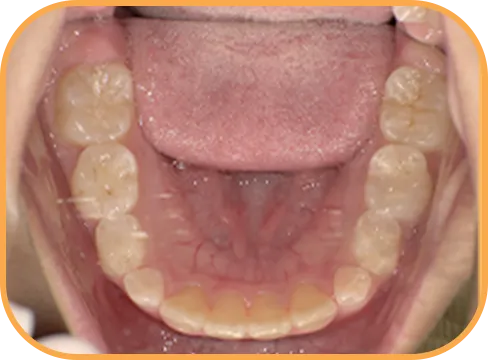

• Before

• 下 顎

治療前下顎からの歯の様子

主 訴

前歯ガタガタ、前歯が大きい

治療内容

インビザライン・ファースト

治療期間

7か月

治療費(税別)

450,000円+診断料5,000円

リスク・副作用

• 親知らずの影響や加齢などによって、凸凹が生じる可能性があります。

• 治療の初期段階では痛みや不快感が生じやすくなりますが、1週間前後で慣れます。

• 顎の成長発育によって、噛み合わせや歯並びが変化する可能性があります。

• 状況により当初予定した治療計画を変更する可能性があります。